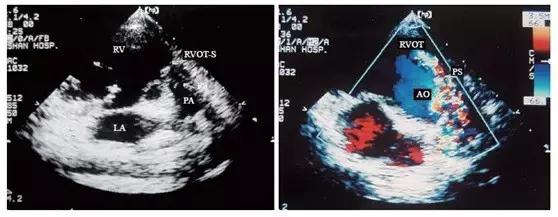

3.由于法洛四联症患者的漏斗隔前移,因此还可见右心室流出道明显缩小,右心室壁和右心室流出道壁明显增厚。在肺动脉长轴切面上,可显示大多数患者肺动脉瓣瓣环和肺动脉主干较细,其程度是决定是否进行跨肺动脉瓣瓣环补片手术的重要因素。合并肺动脉瓣狭窄的患者还可见肺动脉瓣增厚,开放受限,收缩期呈圆隆状。

4.彩色多普勒血流显像显示肺动脉内有五彩镶嵌的细窄射流束,提示肺动脉瓣口狭窄。射流束近端的直径取决于肺动脉瓣狭窄的程度,狭窄越严重,射流束就越细。然而必须明确的是,在肺动脉口重度狭窄的患者,肺动脉内有时可无明显血流信号存在。肺动脉瓣上狭窄的患者肺动脉主干内可见有嵴状凸起。